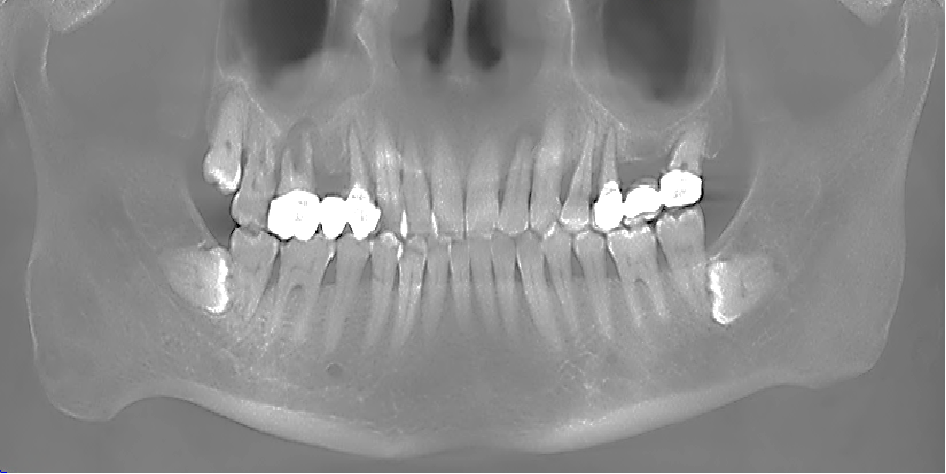

术前CBCT

21颊侧牙槽骨吸收至根尖,腭侧牙槽骨吸收至根尖1/3,根周可见低密度影。牙槽嵴宽度6.41mm。

局部反合、患牙长期牙周病变,骨质缺损,但软组织无明显缺失,为II类拔牙窝形态。

22冠状位CBCT情况

唇舌牙槽嵴宽度6.41mm,垂直骨缺失1/2,软组织无垂直向缺失。